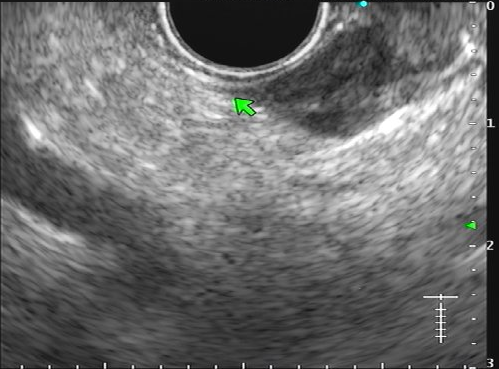

Figuras 1 e 2. Imagem endoscópica em visão direta de lesão protrusa entre pequena curvatura e parede posterior de corpo gástrico proximal, revestida por mucosa com superfície regular, normocorada e íntegra. A imagem ecoendoscópica demonstra lesão com ecogenicidade hipoecoica, ecotextura homogênea, formato ovalado, sem características internas, sem vascularização ao doppler, limites precisos, contornos regulares, medindo aproximadamente 20 x 6 mm e inserida em camada muscular própria. Punções ecoguiadas foram realizadas com agulha FNB, sendo o anatomopatológico e imuno-histoquímica compatíveis com GIST gástrico. Fonte: arquivos do Instituto do Câncer do Estado de São Paulo (ICESP/HCFMUSP)Figuras 1 e 2. Imagem endoscópica em visão direta de lesão protrusa entre pequena curvatura e parede posterior de corpo gástrico proximal, revestida por mucosa com superfície regular, normocorada e íntegra. A imagem ecoendoscópica demonstra lesão com ecogenicidade hipoecoica, ecotextura homogênea, formato ovalado, sem características internas, sem vascularização ao doppler, limites precisos, contornos regulares, medindo aproximadamente 20 x 6 mm e inserida em camada muscular própria. Punções ecoguiadas foram realizadas com agulha FNB, sendo o anatomopatológico e imuno-histoquímica compatíveis com GIST gástrico. Fonte: arquivos do Instituto do Câncer do Estado de São Paulo (ICESP/HCFMUSP)Figuras 3 e 4. Imagem endoscópica em visão direta de abaulamento de parede em segunda porção duodenal distalmente à papila duodenal maior, revestida por mucosa com íntegra, de coloração amarelada e superfície regular. A ecoendoscopia demonstra lesão com ecogenicidade hiperecoica, ecotextura homogênea, formato arredondado, medindo cerca de 10 mm no maior eixo, com limites precisos, contornos regulares, medindo cerca de 10 mm no maior diâmetro e inserida em camada submucosa, sendo os achados endoscópicos e ecoendoscópicos compatíveis com lipoma.Figuras 3 e 4. Imagem endoscópica em visão direta de abaulamento de parede em segunda porção duodenal distalmente à papila duodenal maior, revestida por mucosa com íntegra, de coloração amarelada e superfície regular. A ecoendoscopia demonstra lesão com ecogenicidade hiperecoica, ecotextura homogênea, formato arredondado, medindo cerca de 10 mm no maior eixo, com limites precisos, contornos regulares, medindo cerca de 10 mm no maior diâmetro e inserida em camada submucosa, sendo os achados endoscópicos e ecoendoscópicos compatíveis com lipoma.Fig. 5. Imagem endoscópica em visão direta de lesão protrusa em parede anterior de antro gástrico proximal, revestida por mucosa normocorada, com superfície regular, sendo sugestiva de lesão subepitelial.Fig. 6. A ecoendoscopia evidencia lesão com ecogenicidade hipoecoica, ecotextura predominantemente homogênea, formato arredondado, limites precisos, bordos regulares, medindo aproximadamente 13,4 x 12 mm, sem focos hiperecoicos ou calcificações no interior e inserida na camada muscular própria. Punções ecoguiadas foram realizadas com agulha FNB, sendo anatomopatológico e imuno-histoquímica confirmando schwanomma gástrico.Fig. 7 e 8. Imagem de esofagogastroduodenoscopia demonstra lesão protrusa em papila duodenal maior revestida por mucosa enantemática e com superfície com três erosões recobertas por fibrina.Fig. 7 e 8. Imagem de esofagogastroduodenoscopia demonstra lesão protrusa em papila duodenal maior revestida por mucosa enantemática e com superfície com três erosões recobertas por fibrina.Fig. 9 e 10. Imagem à ecoendoscopia demonstra lesão com formato ovalado, ecogenicidade hipoecoica, ecotextura heterogênea, com contornos regulares, sem adenopatia adjacente, sem vascularização ao doppler, sem características internas, medindo cerca de 20 x 11 x 24 mm, inserida na camada submucosa, não havendo acometimento da muscular própria. Foram realizadas punções ecoguiadas com agulha FNA 22 gauge, sendo o anatomopatológico e imunohistoquímica compatíveis com tumor neuroendócrino de papila duodenal bem diferenciado grau 1.Fig. 9 e 10. Imagem à ecoendoscopia demonstra lesão com formato ovalado, ecogenicidade hipoecoica, ecotextura heterogênea, com contornos regulares, sem adenopatia adjacente, sem vascularização ao doppler, sem características internas, medindo cerca de 20 x 11 x 24 mm, inserida na camada submucosa, não havendo acometimento da muscular própria. Foram realizadas punções ecoguiadas com agulha FNA 22 gauge, sendo o anatomopatológico e imunohistoquímica compatíveis com tumor neuroendócrino de papila duodenal bem diferenciado grau 1.Fig. 11 e 12. Esofagogastroduodenoscopia demonstra abaulamento de parede anterior de corpo gástrico proximal, com mucosa normocorada, superfície regular com depressão central, sendo compatível com lesão subepitelialFig. 11 e 12. Esofagogastroduodenoscopia demonstra abaulamento de parede anterior de corpo gástrico proximal, com mucosa normocorada, superfície regular com depressão central, sendo compatível com lesão subepitelialFig. 13 e 14. Ecoendoscopia demonstrou formação com ecogenicidade hipoecoica, ecotextura homogênea, formato ovalado, limites bem definidos, contornos regulares, medindo aproximadamente 13 mm e inserida na camada submucosa. Lesão foi submetida a ressecção endoscópica transmural com dispositivo FTRD. A histopatologia e imunohistoquímica confirmaram TNE gástrico bem diferenciado grau 2.Fig. 13 e 14. Ecoendoscopia demonstrou formação com ecogenicidade hipoecoica, ecotextura homogênea, formato ovalado, limites bem definidos, contornos regulares, medindo aproximadamente 13 mm e inserida na camada submucosa. Lesão foi submetida a ressecção endoscópica transmural com dispositivo FTRD. A histopatologia e imunohistoquímica confirmaram TNE gástrico bem diferenciado grau 2.